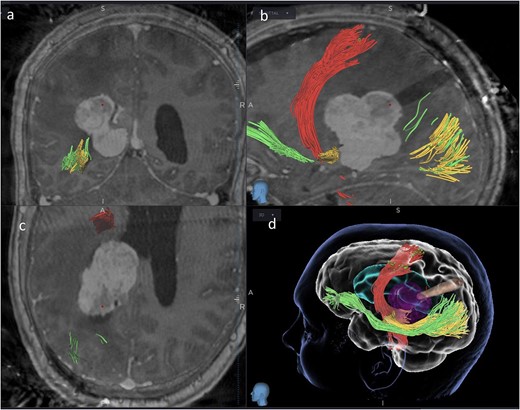

Intraoperative neurophysiology monitoring (IONM) was performed throughout the case using two subdural strips, placed over the motor and occipital cortices following craniotomy. At the end of the procedure (Fig. 4a), CST was identified with subcortical stimulation at 8 mA, and both visual and motor evoked potentials (VEPs and MEPs) were stable (Fig. 4c). An external ventricular drain (EVD) was left in place. Indocyanine green angiography demonstrated no injury to nearby vascular structures (Fig. 4b).

(a) Final microscopic view of the brain surface under bright light: the entry point of the operative corridor is visible at the level of the cortex, in the sulcus. (b) Microscopic final intraoperative view of the brain surface after indocyanine green injection: the vessels are represented without evidence of flow reduction or interruption. (c) Final screenshots of the intra-operative neurophysiology monitoring recorded with stable MEPs and VEPs responses (baseline in red).